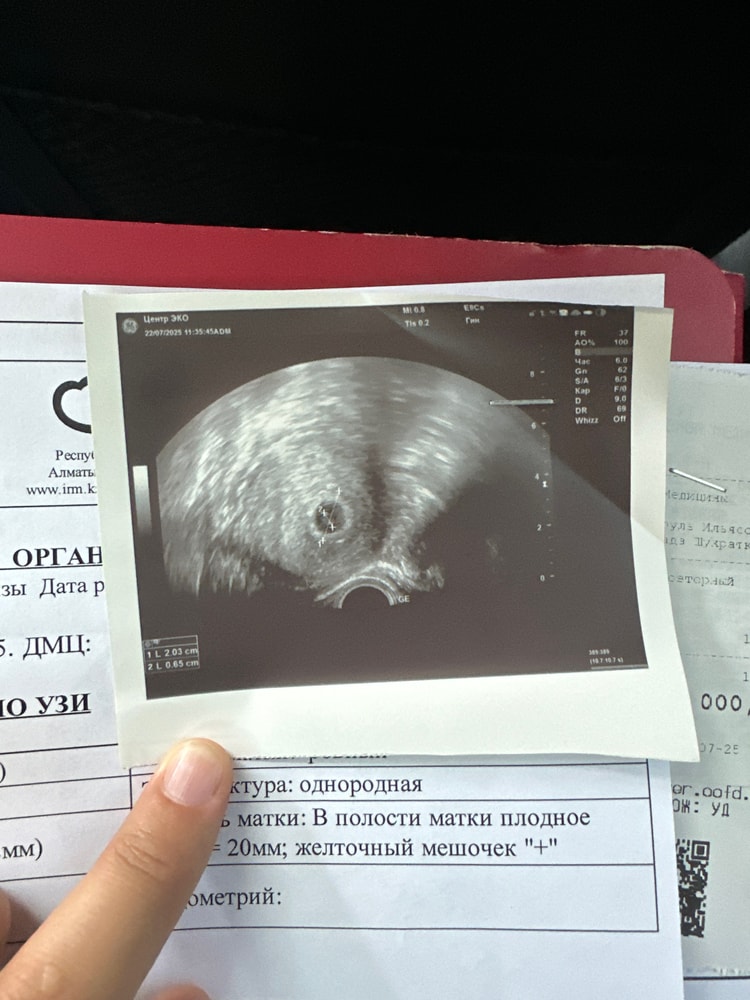

Шахризада в ЭКО-мама 5 месяцев 1 узи на 22 дпп Я БЕРЕМЕННА ! На узи плодное яйцо 20мм и желточный мешочек +след узи 7 августа Посмотрите еще 20 записей на эту тему Отменить Ответить Конфета Поздравляю! Такой прям ровненький, круглый мешочек, прелесть🙂 23.07.2025 Ответить Шахризада Конфета, спасибо🫰🏻 23.07.2025 Ответить Maryam Поздравляю, удачной беременности 🙏🌸 А эмбрион был виден? 23.07.2025 Ответить Шахризада Maryam, спасибо🫰🏻 эмбриона не видно ) через 2 недельки увидим) 23.07.2025 Ответить Maryam Шахризада, удачи вам❤️🙏 23.07.2025 Ответить Шахризада Maryam, спасибоо🫰🏻 23.07.2025 Ответить Первый скрининг 6дпп тест Чаты Беременных Выберите чат: Январята-2026 Февралята-2026 Мартята-2026 Апрелята-2026 Майчата-2026 Июнята-2026 Июлята-2026 Августята-2026